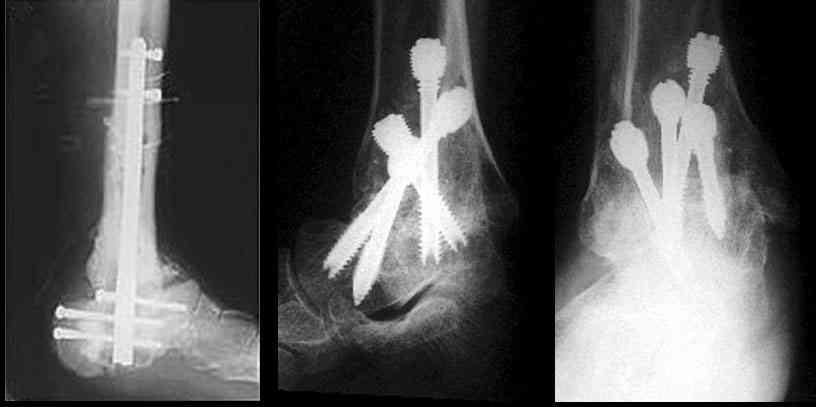

Можно: 65-летняя пациентка, оперирована по поводу несросшегося в гипсе перелома лодыжек с патологической вальгусной установкой стопы и выраженным нарушением опрной функции. Оперирована через 6 месяцев после травмы. Рентгенограммы через 4 месяца после операции.

Уважаемый А.Семенистый. Складывается впечатление, что вы выполнили трехсуставный артродез, уж больно длинные блокирующие винты. Не мешают ли они пациентке при ходьбе?

Да конечно винты длинноваты! Мешают ли ходить? Во всяком случае субьективно пациентка удовлетворена. Ходит, естевственно, хуже чеи до травмы, но намного лучше, чем до операции.